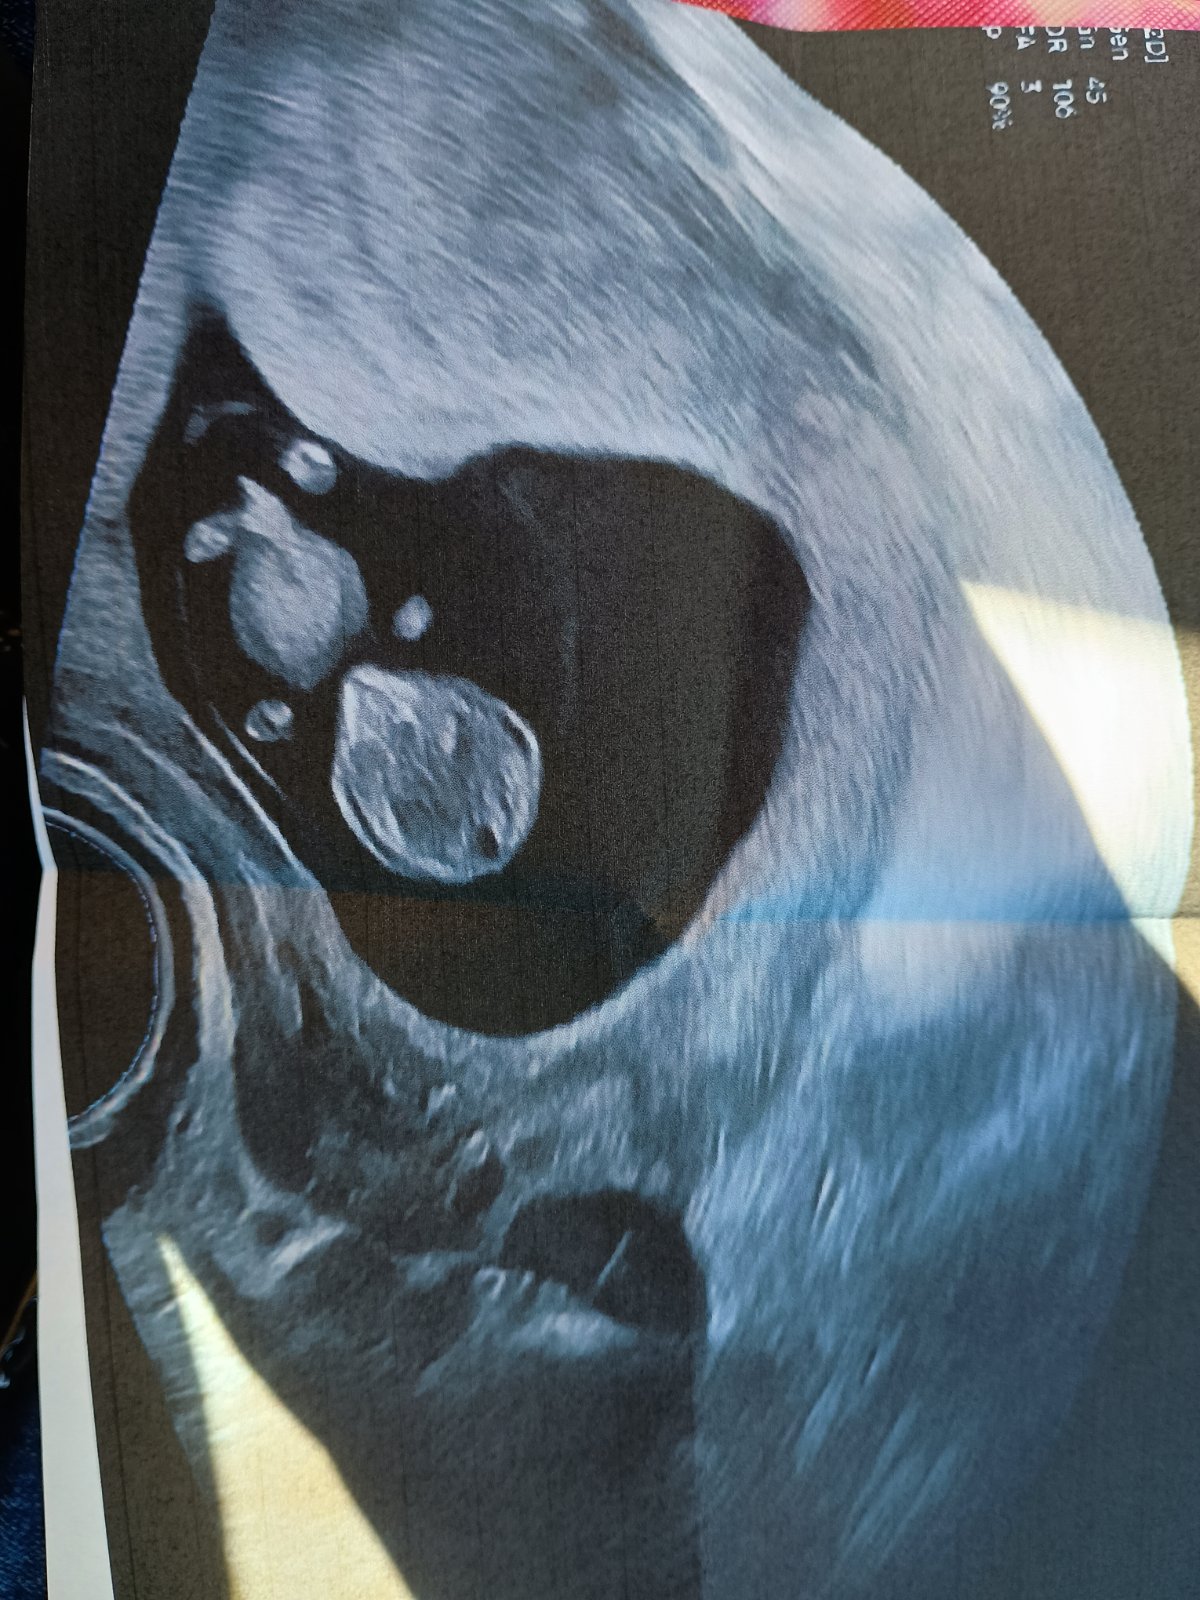

Holky já mám takovou radost 🥳🤩 Dneska jsem byla na kontrole. Všechno je v pořádku, mimčo krásně roste. Když ultrazvuk začal, mimčo tam zrovna mělo diskotéku, mávalo divoce ručičkama a nožičkama. A hned potom se hezky zklidnilo, aby jsme si ho tedy prohlédli a doktorka ho mohla v klidu změřit 😄 Je hodný už takhle v bříšku, snad mu to zůstane i po porodu 😁 Jsem celá naměkko 😍

Jé, to je pěkná fotka.